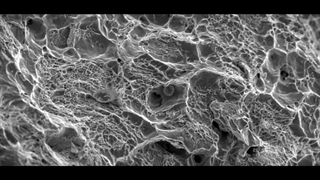

آلودگی به ویروس hpv